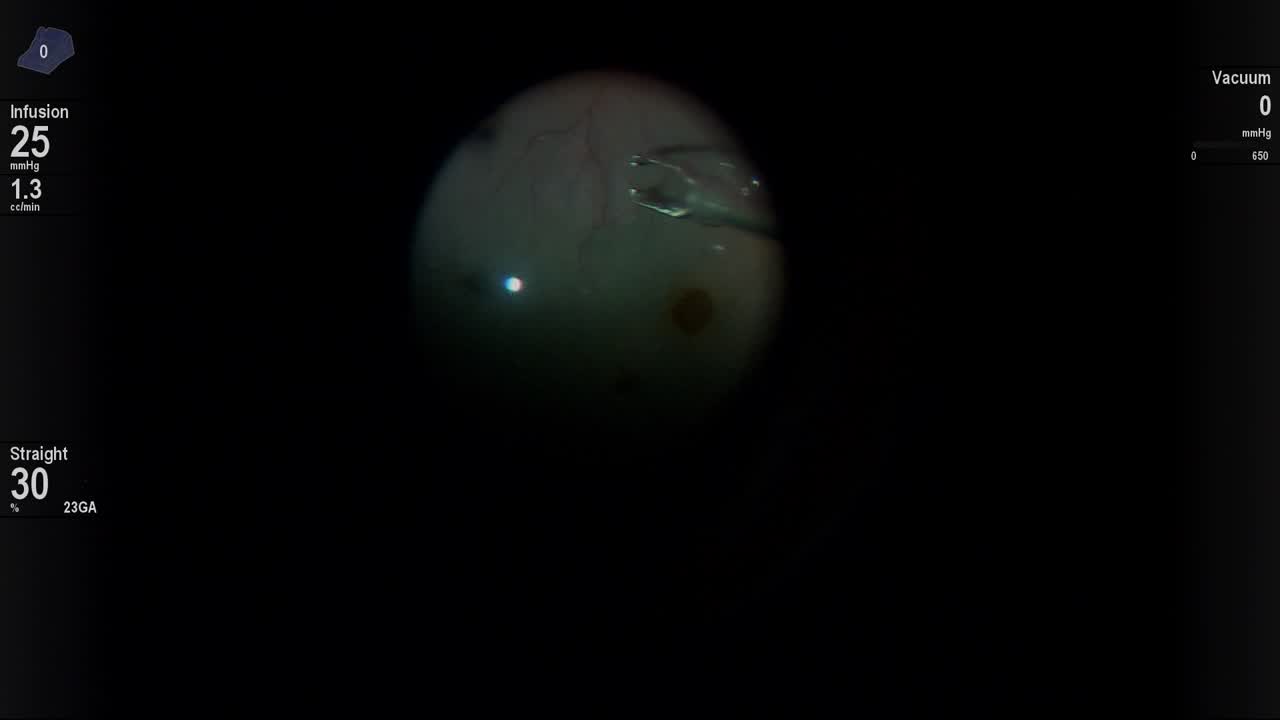

Valved trocar insertion

Kourous A. Rezaei MD